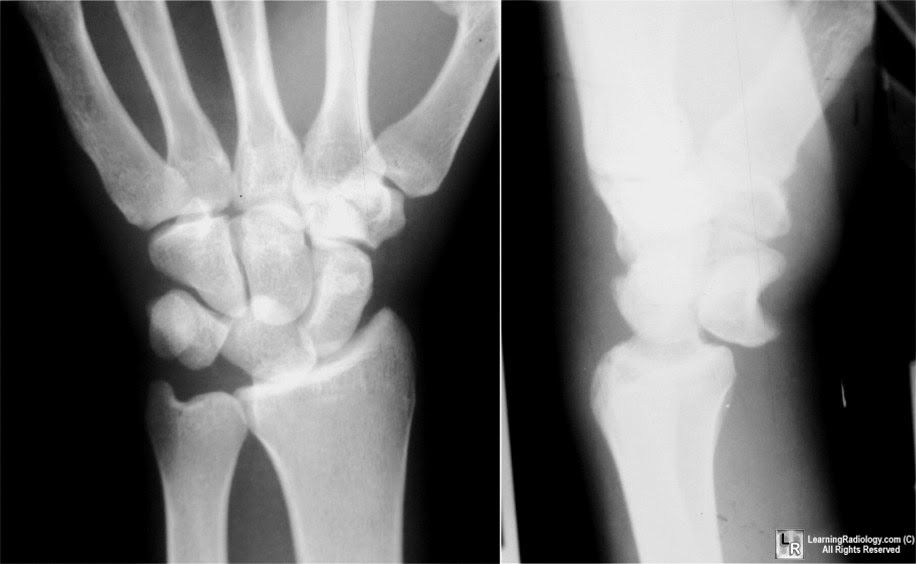

Lunate dislocation with avulsed triquetral fracture A case report

Lunate dislocation with avulsed triquetral fracture A case report What Is A Lunate Bone What is the lunate bone. The hand has eight carpals. It articulates with the distal radius, the scaphoid, the capitate, and the tfcc. It’s classified as a short bone and includes the following bony. It is situated in the center of the proximal row of carpal bones. These small bones comprise the wrist area between the bones of the forearm. What Is A Lunate Bone.

Lunate Dislocation XRay Annotated JETem 2017 JETem What Is A Lunate Bone the lunate bone is part of the proximal carpal row and is well protected within the lunate fossa on the distal radial articular surface. The lunate is one of eight carpal bones that form part of the wrist joint. Os lunatum), also known as the semilunar bone, is one of the eight carpal or wrist. The lunate is one. What Is A Lunate Bone.

ON RADIOLOGY Lunate bone Dislocation What Is A Lunate Bone It is situated in the center of the proximal row of carpal bones. The lunate bone is found in the center of the proximal. the lunate bone (semilunar bone) is one of the eight carpal bones of the hand. It articulates with the distal radius, the scaphoid, the capitate, and the tfcc. the lunate bone is one of. What Is A Lunate Bone.

Lunate dislocation with scaphoid fracture ORTHO radiology What Is A Lunate Bone Os lunatum), also known as the semilunar bone, is one of the eight carpal or wrist. the lunate bone is part of the proximal carpal row and is well protected within the lunate fossa on the distal radial articular surface. The lunate bone is found in the center of the proximal. the lunate bone is one of the. What Is A Lunate Bone.